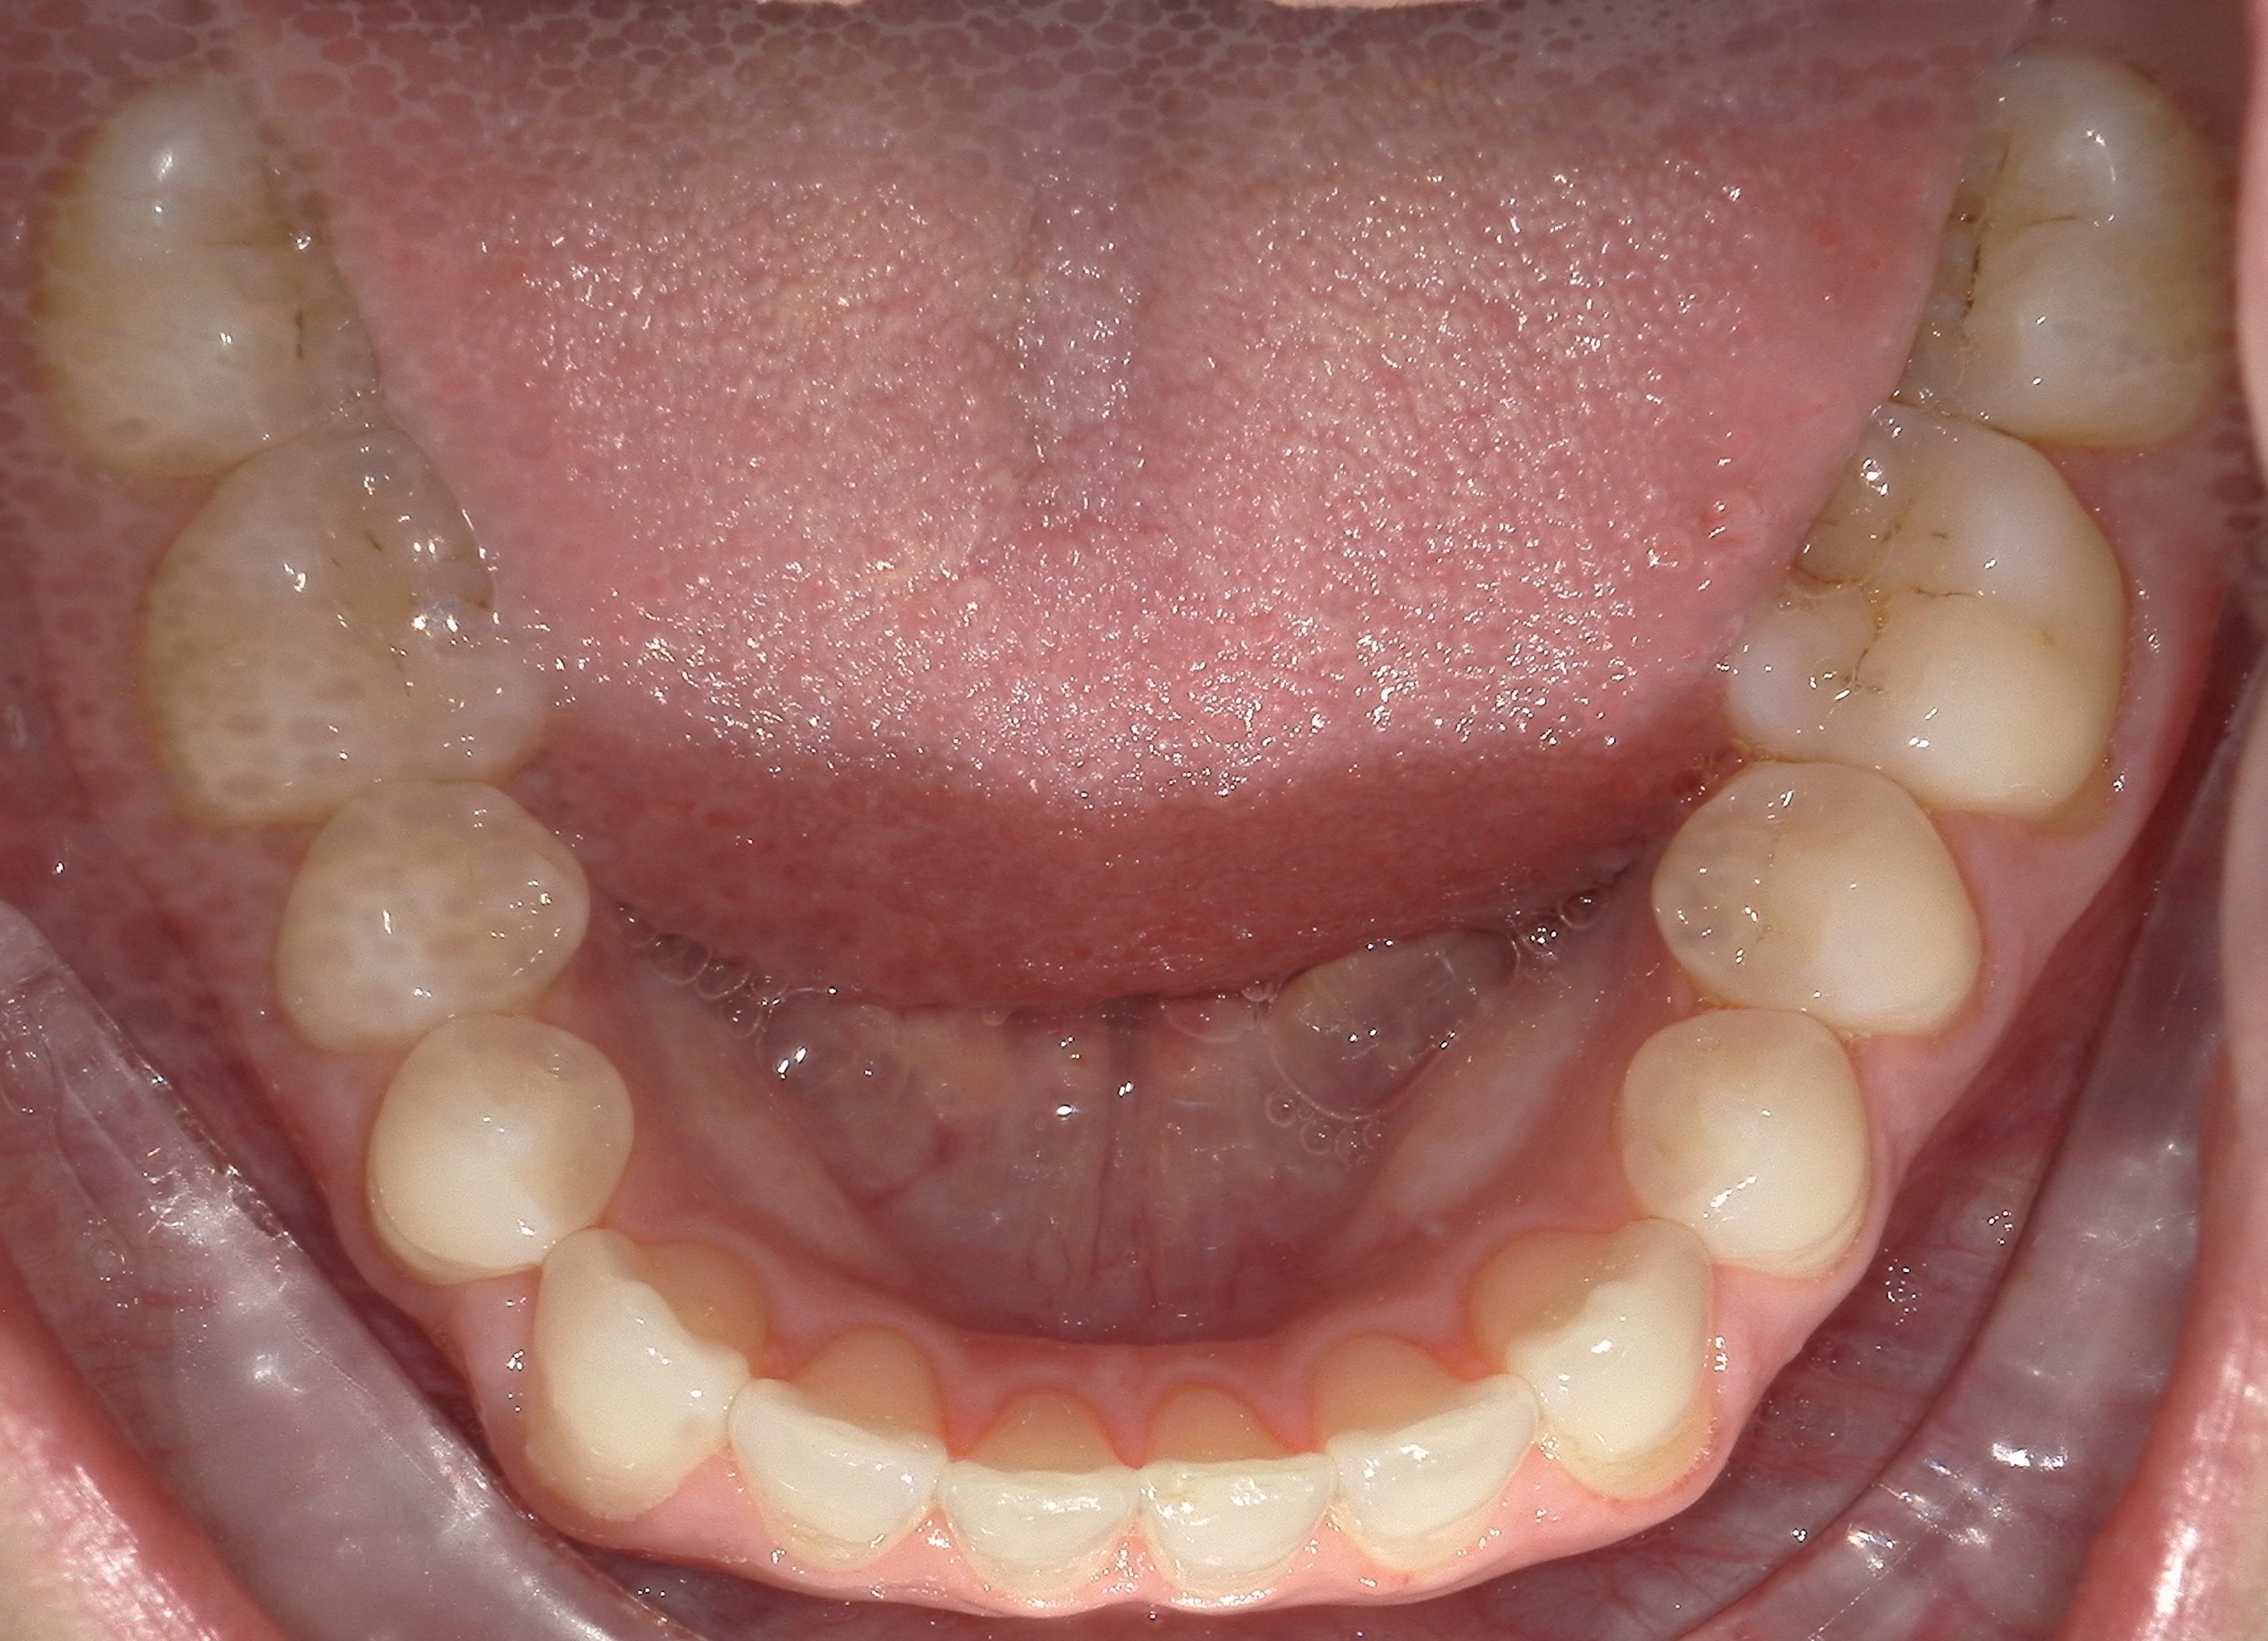

Initial treatment

INTRAORAL

Diganosis: Moderate lower anterior crowding, square and narrow maxilla, rotated #19

Adjuncts: Attachments